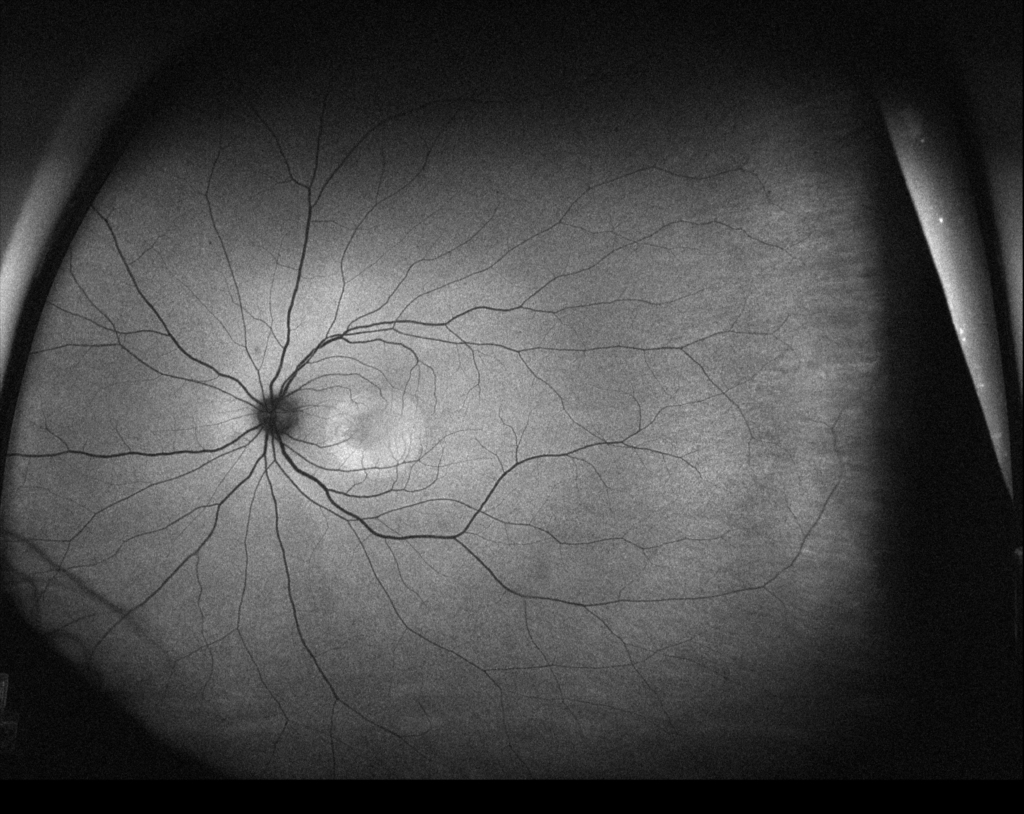

黄白色病巣に一致して早期に点状の過蛍光点がみられる。